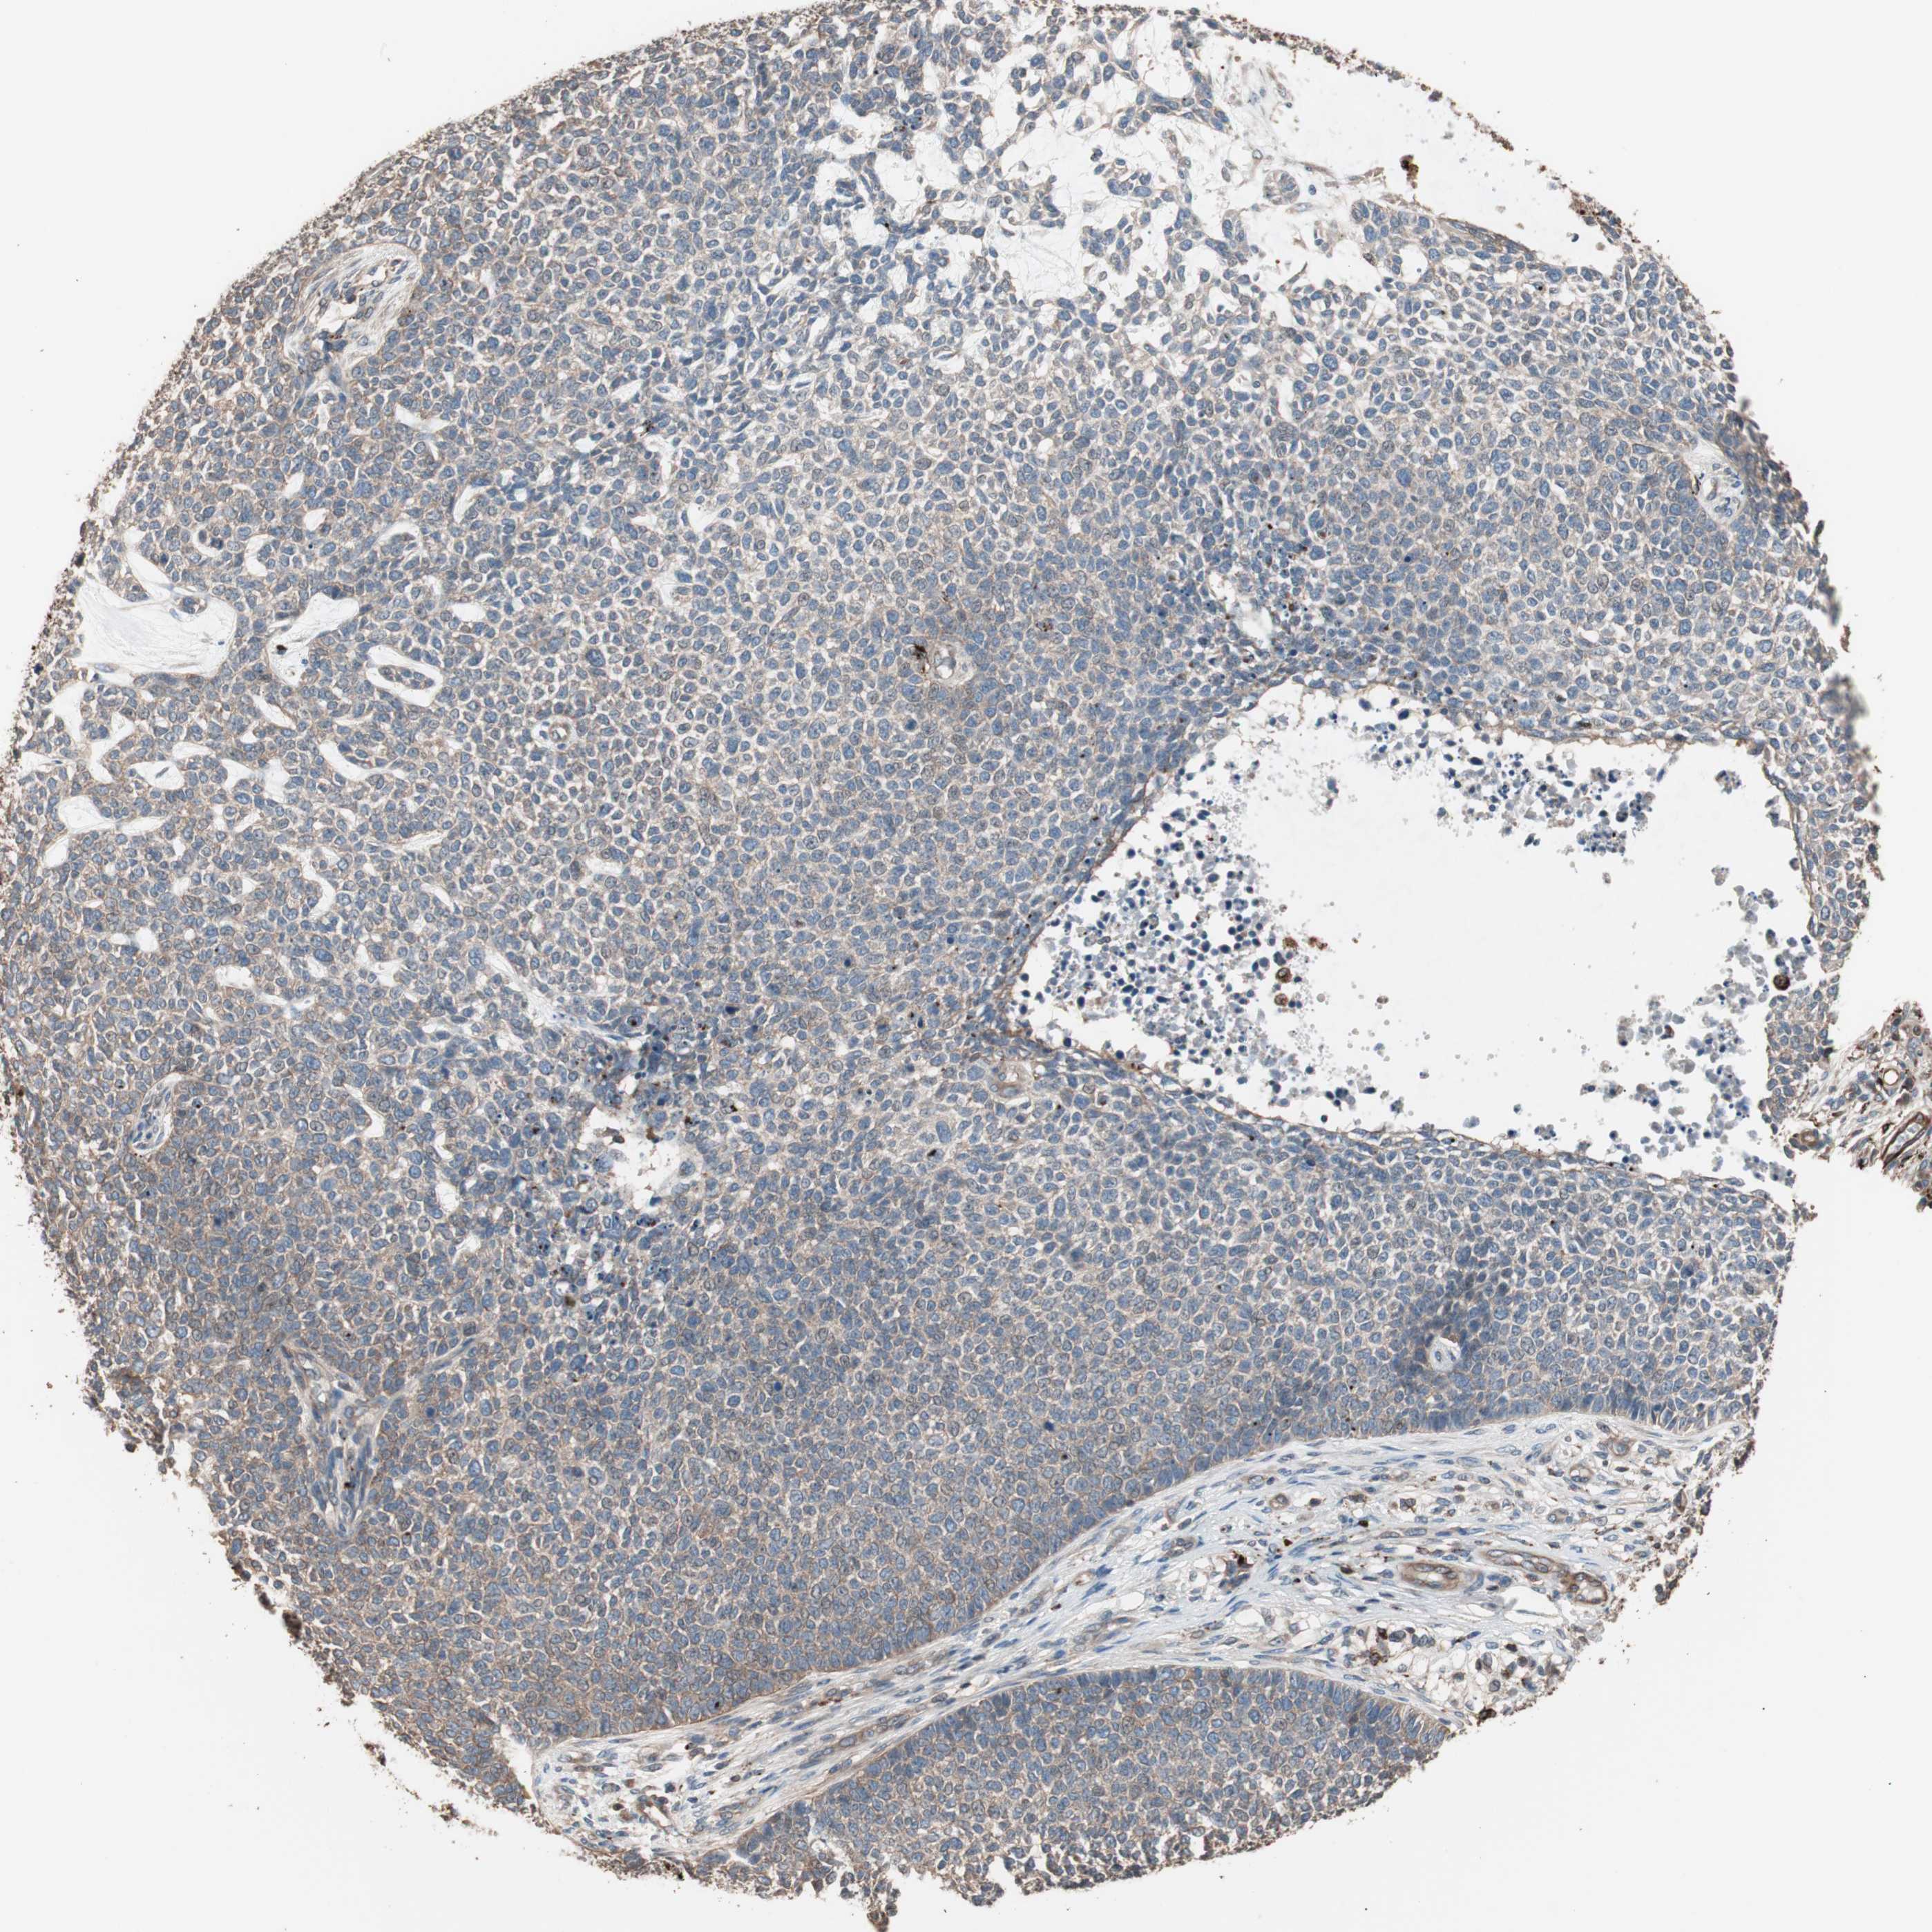

SKIN CANCER - Protein expressioni

A mouse-over function shows sample information and annotation data. Click on an image to view it in a full screen mode. Samples can be filtered based on level of antibody staining by selecting one or several of the following categories: high, medium, low and not detected. The assay and annotation is described here.

Antibody stainingi

Antibody staining in the annotated cell types in the current human tissue is reported as not detected, low, medium, or high, based on conventional immunohistochemistry profiling in selected tissues. This score is based on the combination of the staining intensity and fraction of stained cells.

Each image is clickable and will lead to virtual microscopy that enables deeper exploration of all samples and also displays staining intensity scores, fraction scores and subcellular localization as well as patient and tissue information for each sample.

Antibody HPA006543

Staining

Low

Intensity

Weak

Quantity

75%-25%

Location

Cytoplasmic/membranous

Papilloma, NOS